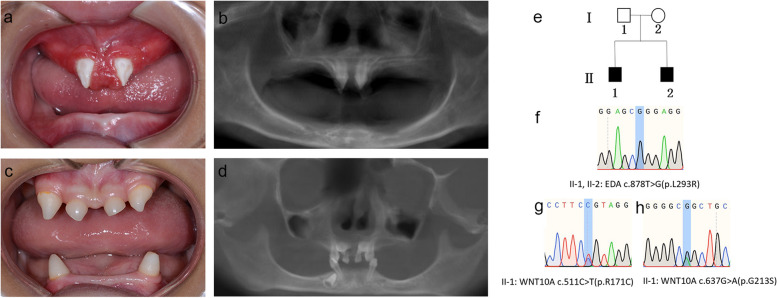

兩名分別為11歲和8歲的親兄弟因先天性牙齒缺失被轉(zhuǎn)診至同佳學(xué)基因具有合作關(guān)系的武漢大學(xué)口腔中心就診。經(jīng)患兒母親及兩名患兒本人簽署知情同意書后,醫(yī)護(hù)人員收集了兩位患兒的病史資料,拍攝了相關(guān)臨床照片,并采集了外周靜脈血樣本外送到佳學(xué)基因檢測進(jìn)行致病基因鑒定基因解碼分析。這對兄弟被診斷為低汗性外胚層發(fā)育不良(HED),均表現(xiàn)出典型的臨床特征,包括少牙(hypodontia)、毛發(fā)稀疏(hypotrichosis)、少汗(hypohidrosis)以及面部發(fā)育異常(facial dysmorphism)。有趣的是,哥哥的牙齒發(fā)育不全明顯比弟弟更為嚴(yán)重。哥哥下頜完全無牙,僅保留上頜兩顆中切牙;而弟弟則仍有部分前牙萌出。

體格檢查顯示,這對兄弟均表現(xiàn)出頭發(fā)稀疏、牙齒缺失及汗腺發(fā)育不良(圖1a-d)。兩人均具有X連鎖低汗性外胚層發(fā)育不良(HED)的典型面容特征:鞍鼻、嘴唇厚大、下頜尖翹以及眼周黑眼圈。

口腔檢查及錐形束CT(CBCT)掃描結(jié)果提示,哥哥(II-1)的所有乳牙及大多數(shù)恒牙均先天缺失,僅保留兩顆錐形上中切牙(#11、21)(圖1a-b)。由于下頜牙列完全缺失,他無法正常咀嚼或建立咬合關(guān)系。

弟弟(II-2)尚保留6顆乳牙(#51、53、61、63、73、83)及3顆恒牙胚(#11、21、43)(圖1c-d)。

Fig. 1

圖1:HED兄弟患者的牙齒特征與面部表現(xiàn)

a-b:**兄長(II-1)**的口腔狀況及全景X線片。

c-d:弟弟(II-2)的口腔狀況及全景X線片。

e:家系圖,黑色方塊代表HED患者。

f:DNA測序圖譜顯示兩位兄弟(II-1,II-2)攜帶

EDA基因雜合變異c.878T>G(p.L293R)

g-h:兄長(II-1)同時(shí)攜帶兩個(gè)WNT10A基因雜合變異:c.511C>T(p.R171C)和 c.637G>A(p.G213S)。

在兩兄弟中均檢測到EDA基因c.878T>G(p.L293R)的錯(cuò)義變異,但復(fù)合雜合型WNT10A基因變異(c.511C>T(p.R171C)和c.637G>A(p.G213S))僅在兄長中發(fā)現(xiàn)。

母親臨床表型正常,未出現(xiàn)毛發(fā)、汗腺或牙齒相關(guān)異常。WES檢測顯示其為EDA基因c.878T>G雜合變異及WNT10A基因c.511C>T雜合變異的攜帶者。上述結(jié)果均經(jīng)Sanger測序驗(yàn)證(圖1e-h)。